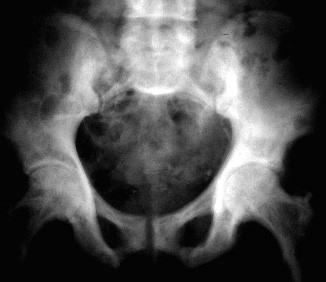

Los cambios radiográficos son patognomónicos, y suelen llevar al diagnóstico. La Fig. 80-2 muestra un húmero; la Fig. 80-3 una vértebra, la Fig. 80-4 una pelvis, y la Fig. 80-5 un cráneo afectados por la enfermedad de Paget; la Fig. 80-6 es el estudio tomográfico del mismo cráneo.

Fig. 80-4. En la placa de pelvis se observa la densificación de los huesos ilíacos, sobre todo el izquierdo.